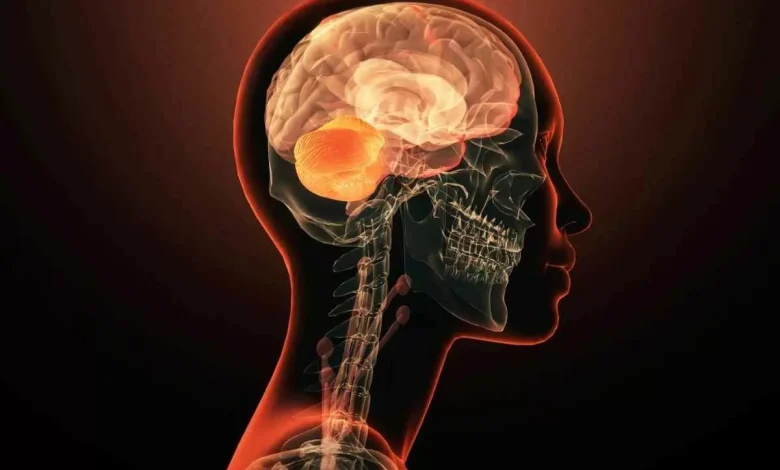

سالها فکر میکردیم بیماریهای روانی نتیجهی هزاران ژن و دهها عامل محیطیاند؛ یک آشوب زیستی که هیچوقت نمیشود آن را به یک قطعهی واحد نسبت داد. اما حالا ژنی پیدا شده که این قواعد را زیر پا میگذارد: GRIN2A. جهشی کوچک در این ژن میتواند مسیر رشد شبکههای عصبی را آنقدر تغییر بدهد که مغز وارد الگوهای رفتاری و ادراکی کاملاً متفاوت شود؛ چیزی که تا همین دیروز، غیرممکن به نظر میرسید.

راز ماجرا در گیرندههای NMDA است؛ کانالهای ظریف و حساس روی نورونها که نقششان در یادگیری، حافظه و ادراک مثل نقش ترانزیستور در یک مدار است. ژن GRIN2A یکی از قطعات اصلی برای ساخت این گیرندههاست. وقتی این ژن دچار جهش میشود، مغز بهجای اینکه سیگنالها را هماهنگ و صاف عبور دهد، وارد یک حالت «عدمتعادل الکتروشیمیایی» میشود: سیناپسها بیشفعال یا کمفعال میشوند، مسیرهای عصبی بههمریخته بازآرایی میشوند، و برخی الگوهای شناختی ممکن است بهطور کامل از مسیر طبیعی خارج شوند. نتیجه؟ در بعضی افراد علائم روانی شدید، آن هم از سنین بسیار پایین.